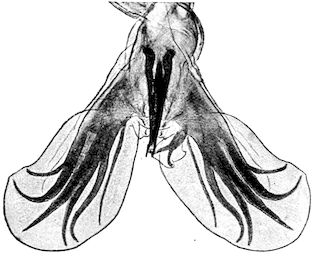

Fig. 8.—Transverse section through the middle region of the face in a pig suffering from osseous cachexia.

18In the final stages, the bones may be cut with a knife, and a time arrives when bony tissue seems completely to have disappeared; thus, as shown in Fig. 8 herewith, it was possible to cut the entire head of a pig into thin slices without the slightest difficulty. All parts of the head had been affected by the softening change.

114. The fourth phase, or period of osteomalacia, i.e. softening of the bones, is also the last. It is rarely seen in large animals like horses and oxen, because accidents so often accompany the preceding stages and necessitate slaughter; but it is common in goats and pigs.

In this phase the bones become elastic, soft and depressible, yielding to the pressure of the operator’s fingers.

Fig. 4.—Deformity of the face in the horse shown in Fig. 2.

The flat bones are particularly liable to this change, which is common to domesticated animals. The bones of the head are the first to suffer; later those of the pelvis. The lower jaw becomes swollen, particularly about the centre of the branches which may attain three, four, or five times, their normal thickness.

The depression in the submaxillary space disappears. The upper jaw undergoes similar changes, becoming deformed and thickened until the cavities of the sinuses and the hollow appearance of the palate are lost, while the face is so changed that it cannot be recognised as that of a horse, goat, etc.

The molar teeth are almost buried, their tables alone being visible at the bottom of a depression, the edges of which rise above the neighbouring parts (pig).

Mastication is clearly impossible, the jaws appear paralysed, the muscles powerless, and only swallowing is possible, a fact which explains why life is only prolonged to this stage in animals which can be fed with a spoon or bottle (pigs and goats). The bones of the cranium, although greatly changed in texture, are always less deformed than those of the face.

The changes are such that it is often easy with a mere post-mortem knife to cut the head completely in two. Osseous tissue, properly so-called, has disappeared.

All the constituent tissues, with the exception of the skin and muscles, i.e., the bone, periosteum and aponeuroses, have the appearance and consistence on section of the fibro-lardaceous tissue seen in chronic inflammation.